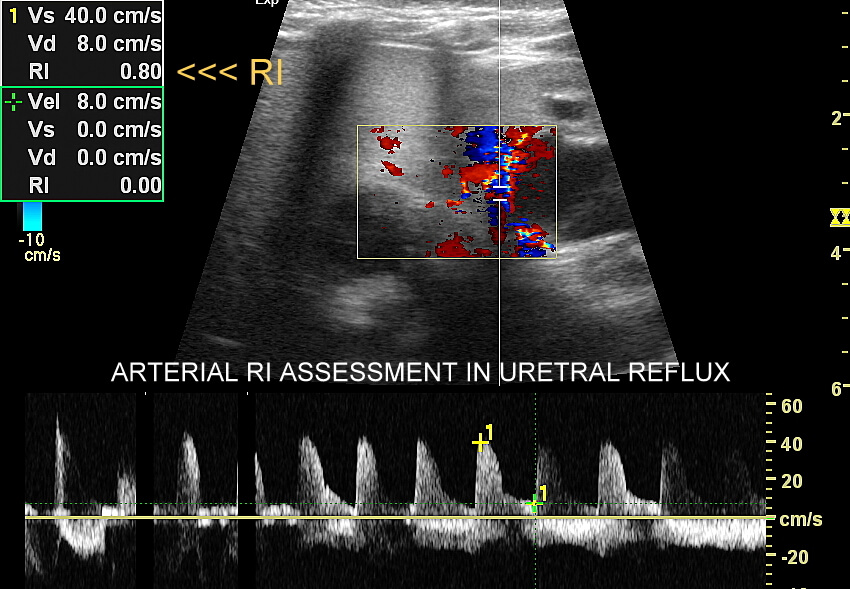

WSKAŹNIK OPORU RI

Seria USG w 5 minut! Wskaźnik oporu (RI, Resistance Index), zwany także wskaźnikiem Pourcelot’a, to parametr obliczany ze szczytowej (PSV, Peak Systolic Velocity) oraz z końcowo-rozkurczowej (EDV, End Diastolic Velocity) wartości prędkości przepływu w naczyniu krwionośnym w obrazowaniu Dopplerem spektralnym wg wzoru:

RI = PSV-EDV / PSV

Wartości RI w praktyce oblicza się zwykle w obrębie naczyń tętniczych. Jak nazwa wskazuje wskaźnik oporu określa opór jakiemu podlega przepływ krwi przez dany obszar, tj. tkankę lub organ, i z tego względu RI ma szerokie zastosowanie w ich ocenie funkcjonalnej. Przykładowe zastosowania RI obejmują ocenę biologii wzrostu guza, wydolności nerek, zastoju moczu w układzie kielichowo-miedniczkowym, czy obrzęku mózgu. Jak być może zauważyliście, wskaźnik RI wykorzystuje się głównie przy ocenie narządów miąższowych a nie elementów układu mięśniowo-szkieletowego; również w mniejszym stopniu samych naczyń tętniczych, w wyjątkami, np. do oceny przetok dializacyjnych.

Narządy miąższowe w zależności od swojej funkcji i wtórnie od poziomu swojego metabolizmu posiadają różnorodne zapotrzebowanie na tlen i glukozę, a tym samym na objętość przepływającej przez nie krwi. Narządami wewnętrznymi o wysokim poziomie metabolizmu są mózg, tarczyca, wątroba, nerka, śledziona, serce. Hemodynamikę przepływu wieńcowego w sercu wyłączamy z omówienia w niniejszym artykule. W pozostałych wymienionych narządach wewnętrznych o wysokim bazowym metabolizmie opór przepływu tętniczego jest niski, tj. wskaźnik oporu RI znajduje się w zakresie 0,5-0,7; mówimy wtedy o tzw. przepływie niskooporowym. Wartości RI od 0,70 do 0,75 należą do szarej strefy, a wartości RI >0,75 określane są jako przepływ wysokooporowy. Fizjologicznie wyższy opór obserwujemy przy szybszej akcji serca, stąd u niemowląt wartości RI w narządach miąższowych mogą być nieco wyższe aniżeli fizjologicznie u zdrowych dorosłych, ale wciąż w zakresie referencyjnym. Zauważcie, iż cały czas mowa jest o narządach wewnętrznych. W przypadku struktur układu mięśniowo-szkieletowego, którego w tym artykule dokładnie nie omawiamy, fizjologiczne opory przepływu tętniczego są zwykle o wysokim lub o bardzo wysokim oporze; przykładowo RI do mięśni w kończynach dolnych wynosi zwykle 1.

Patologicznie zwiększony wskaźnik RI w narządach miąższowych obserwuje się przykładowo w chorobach miąższu nerki i jej niewydolności, znacznie zwiększonym ciśnieniu w układzie kielichowo-miedniczkowym w wyniku blokady odpływu moczu, czy w podwyższonym ciśnieniu śródczaszkowym. Z kolei w zmianach nowotworowych szybko rosnących obserwuje się niskie wartości RI; podobnie w przypadku naczyniaków typu high-flow. Z powyższych względów analiza wskaźnika RI wykorzystywana winna być bardzo szeroko przy multiparametrycznych badaniach USG (MPUS) w transplantologii, nefrologii, hepatologii, intensywnej terapii, onkologii, chirurgii, czy neurologii.